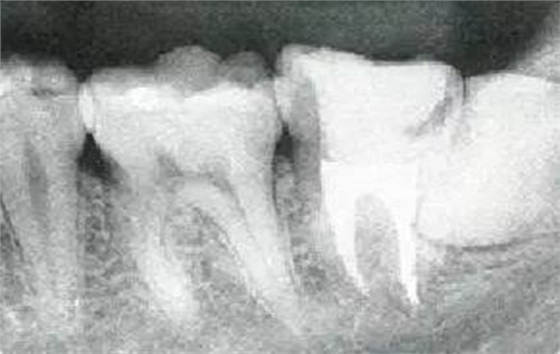

參考病例① 35歲女性

在左下第一磨牙在25歲時(shí)近中處可以看到垂直性的骨吸收,但35歲時(shí)吸收停止,原本沒有見到的遠(yuǎn)中處骨吸收的,現(xiàn)在卻吸收得很嚴(yán)重。

在右下處,原本有大量骨吸收的第一磨牙處的吸收卻變緩慢,原本沒有吸收的第二前磨牙卻出現(xiàn)了吸收。出現(xiàn)吸收的左上第一磨牙的遠(yuǎn)中處,吸收得越來越多了。